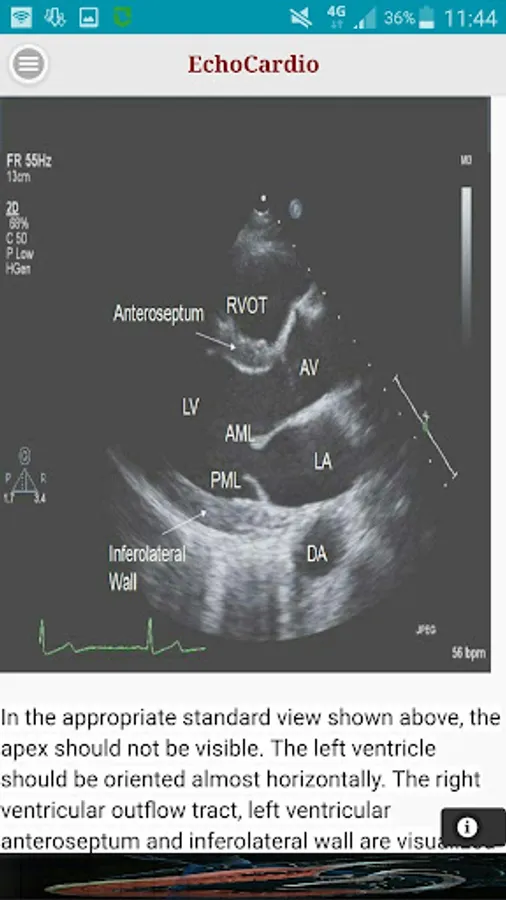

Parasternal Long Axis

Transthoracic echocardiography (TTE) is the most commonly performed cardiac ultrasound examination. A high quality transthoracic echocardiogram can be performed quickly at the bedside and has the potential to comprehensively evaluate left and right ventricular systolic and diastolic function, regional wall motion, valvular heart disease, and diseases of the pericardium.